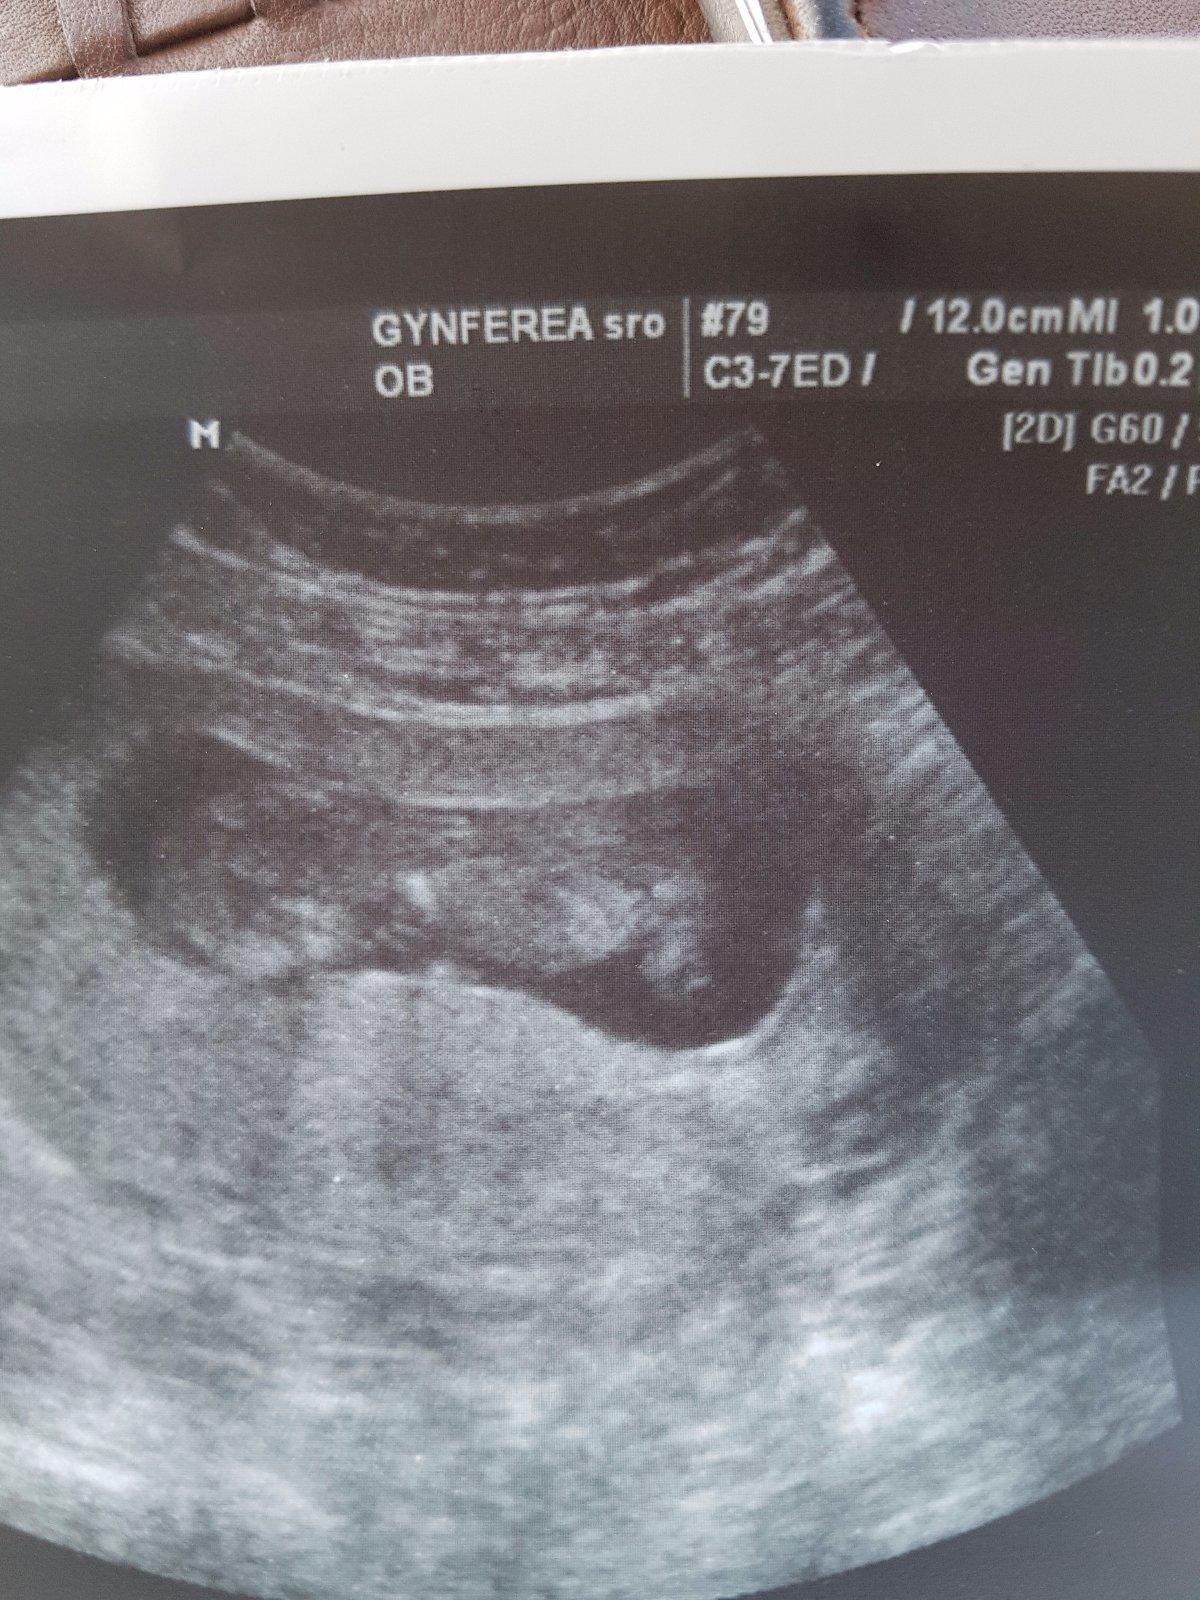

Tak drobčiatko je v pohode .

A spinenie ,ze pokial by sa zosilnilo treba do nemocky ale mam lezat a malo by to prejst,ze teraz dost maternica rastie tak to moze byt tym.

A slubena fotočka 😍